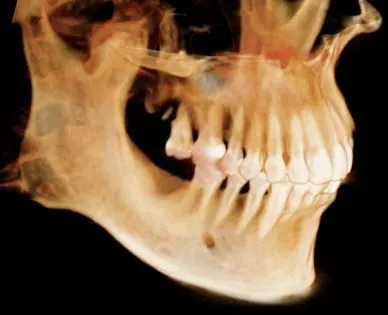

Cone Bean Computer Assembled Tomography

Our office uses the most advanced technology to treat our patients in the most effective way. We use the award-winning i-CAT 3D FLX Cone Beam Computer Assembled Tomography (CBCT) imagining system to acquire the most diagnostic image with less radiation than the average panoramic or traditional x-ray. The dose from this imaging system is 80-95% less than a medical Computed Tomography. With an extremely short scan, typically within five seconds, we can obtain enough data for a comprehensive diagnosis.

The type of radiation produced by the i-CAT is no different than that produced by any other x-ray machine. But with less radiation, one i-CAT scan can replace all of traditional images like panoramic, a lateral cephalogram (head film) and various periapical x-rays in just one click.

i-CAT 3D imaging provides exceedingly beneficial information about the following:

• Less radiation

• More details

• 3D image system

• Precise location of impacted teeth

• Precise measurement of implant placement

• Bone loss visualization

• Medical findings